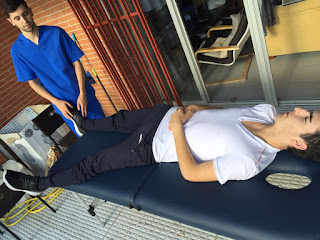

- Fase 3: El paciente se pondrá decúbito supino en la camilla e intentará hacer una abducción de escápulas intentando juntar los hombros repetidas veces.

1.Posición inicial:

2.Posición final: